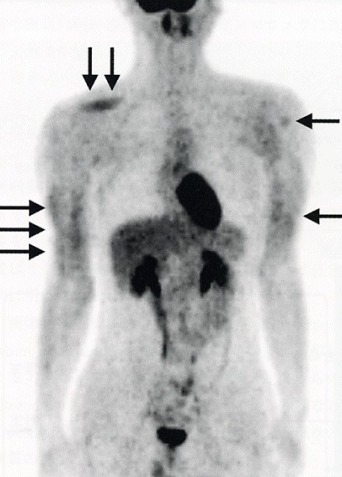

図1に、検査当日、F-18 FDG静注前にダンベルを使ってトレーニングを行った症例のFDG-PET全身像を示す。静注後は安静を確保したが上腕や右肩の筋肉へのFDG集積増加が見られる。

図1 FDG投与前にダンベルでトレーニングをした症例のFDG-PET像。上腕、右肩の筋肉へのFDG集積が増加している(矢印)。心筋、縦隔、肝、腎、尿管、膀胱などへの生理的集積も認められる。(原論文1より引用)